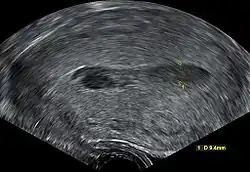

Transvaginal ultrasonography of a hematometra after childbirth, seen as a hypoechoic (darker) area within the uterine cavity. The cervix is located to the left in the image, and the fundus is located to the right.

Although hematometra can often be diagnosed based purely on the patient's history of amenorrhea and cyclic abdominal pain, as well as a palpable pelvic mass on examination, the diagnosis can be confirmed by ultrasound, which will show blood pooled in the uterus and an enlargement of the uterine cavity.[5][6] A pyelogram or laparoscopy may assist in diagnosing any congenital disorder that is suspected to be the underlying cause of the hematometra.[3]